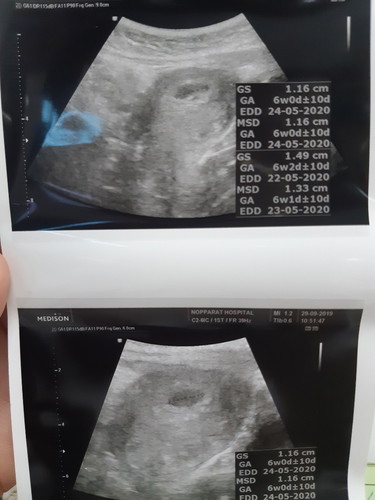

ไปฝากครรภ์มาวันนี้ หมอบอกว่า จากประวัติประจำเดือนลูกน่าจะ 3เดือนกว่า แต่พอ อัลตราซาวนด์แล้วกลับเจอว่ายังเปนถุงน้ำเท่ากับคน อายุครรภ์6สัปดาห์ หมอเลยบอกว่าครั้งหน้านัดใหม่ลูกต้องโตเต็มถุงค่ะ เพราะเมื่อวันพฤหัสบดีที่ผ่านมามีเลือดออกช่องคลอดเล็กน้อย ค่ะ ตอนนี้กังวลมากว่าจะแท้งรึป่าว แม่ๆท่านไหนเคยมีประสบการณ์บ้างค่ะ ส่วนตัวมีลูกมาแล้ว1คน ท้องนี้เปนท้องที่สองค่ะ อายุ26ปีตอนนี้